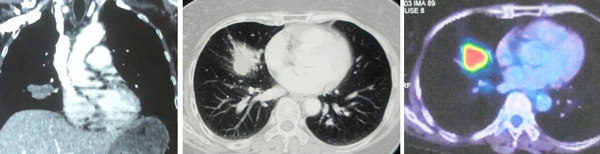

CT scan thorax done in Hospital A, 29 August 2017.

- a suspicious 3.4 x 2.8 x 3.3 cm lump in the lower lobe of his left lung.

CT scan of brain, neck, thorax, abdomen and pelvis done in Hospital C, 26 September 2017.

- lesion at apical segment of left lower lobe of lung and small cavities due to primary carcinoma.

- multiple small metastases in both lungs.

- enhancing lesions at left parietal lobe, vermis and right cerebellum.

- patchy sclerosis of body of T1 vertebrae suggestive of metastasis.

- lymph node at level 4 of neck.

Whole body PET Scan done in Hospital C, 18 January 2018.

- metabolic activity noted in the right (1.8 cm) and left sides of neck (1.9 cm) .

- metabolic activity noted in the left base of the tongue.

- metabolic activity left axillary lymph node (2 cm).

- irregular metabolic active mass (3.2 cm) seen in the apical segment of the lower lobe of left lung.